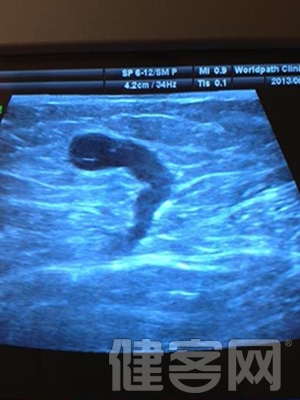

最近有幾例轉診來滬的靜脈曲張術後復發患者。通過超聲定位,發現:交通支病變遺漏和小隱靜脈病變被忽視,是造成術後復發的重要原因,患者不得不再次接受手術。假如術前主刀醫生親自做彩超檢查定位,則可以避免此類復發。

主刀醫生親自做術前超聲檢查定位,是發達國家靜脈曲張治療的常規流程,具有以下的作用:

交通靜脈和小隱靜脈病變往往在外表上不明顯,必須要超聲檢測,但是國內幾乎所有醫院的超聲報告,都缺乏這兩項檢查的描述。因此,容易導致術後復發。

(2)通過彩超定位,可以了解詳細的血流方向和病變發布情況,可以有效減少盲目的切口。

(3)手術醫生親自做術前超聲檢查,可以更有效地對疾病作出判斷,減少並發症。

主刀醫生的手術前彩超檢查,可以使得治療個體化設計,避免無謂的復發和並發症。